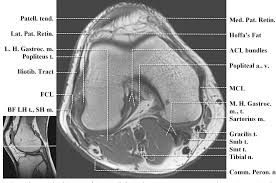

Diz Anatomisi Mri And Mrg Aksiyal

Diz Anatomisi Mri And Mrg Aksiyal from konez.com

Magnetic resonance imaging (mri) is a noninvasive test used to diagnose medical conditions. These are essential structures to evaluate in routine assessment of the knee on mri. Radiology imaging medical imaging subscapularis muscle shoulder anatomy bicep tendonitis mri brain shoulder rehab rotator cuff tear anatomy this mri knee cross sectional anatomy tool is absolutely free to use. Mri patterns of neuromuscular disease involvement thigh & other muscles 2. Free access interactive and dynamic anatomical atlas. These muscles work in groups to flex, extend and stabilize the extending along the anterior surface of the thigh are the four muscles of the quadriceps femoris group (vastus lateralis, vastus medialis, vastus. Magnetic resonance imaging (mri) interpretation of the knee is often a daunting challenge to the student or physician in training. Which are the ligaments that keep it stable? An understanding of normal anatomy and biomechanics of the knee extensor mechanism is necessary to comprehend the imaging of extensor mechanism injuries. Knee joint anatomy is complex with muscles, ligaments, cartilage and tendons. General anatomy and musculoskeletal system. This section of the website will explain. Use the checklist to quiz yourself.

Mri for evaluating knee pain in older patients: The muscles that affect the knee's movement run along the thigh and calf. Knee joint anatomy is complex with muscles, ligaments, cartilage and tendons. Each anatomical structure was labeled interactively. How does the knee joint work? Please email baodo at stanford.edu. The knee joint is most significantly affected by two major muscle groups: These muscles work in groups to flex, extend and stabilize the extending along the anterior surface of the thigh are the four muscles of the quadriceps femoris group (vastus lateralis, vastus medialis, vastus. Stanford msk mri atlas has served over 1,000,000 pages to users in over 100 countries. Robin smithuis and henk jan van der woude. Which are the ligaments that keep it stable? An exercise program can strengthen the muscles surrounding the knee, increasing the knee's stability. Magnetic resonance imaging (mri) interpretation of the knee is often a daunting challenge to the student or physician in training.

They are attached to the femur (thighbone), tibia (shinbone), and fibula (calf bone) by fibrous tissues called ligaments. The journal of musculoskeletal medicine. Current and accurate information for patients about magnetic resonance imaging (mri)of the knee. Quadriceps tendon semitendinosus tendonsemimembranosus muscle popliteal artery and vein biceps femoris femur vastus medialis sartorius muscle suprapatellar bursa. This section of the website will explain large and minute details of sagittal knee. Scroll through the structures to understand the anatomy. Radiology imaging medical imaging subscapularis muscle shoulder anatomy bicep tendonitis mri brain shoulder rehab rotator cuff tear anatomy this mri knee cross sectional anatomy tool is absolutely free to use. An understanding of normal anatomy and biomechanics of the knee extensor mechanism is necessary to comprehend the imaging of extensor mechanism injuries. 4, infrapatellar fat pad of hoffa. Find out how the different structures fit together in our knee diagram the knee joint is the largest and one of the most complex joints in the human body. Located on the posterolateral aspect of the knee joint, extending from the popliteus muscle to the medial aspect of the fibula. Radiology imaging medical anatomy human anatomy and physiology anatomy study. The muscles that affect the knee's movement run along the thigh and calf.